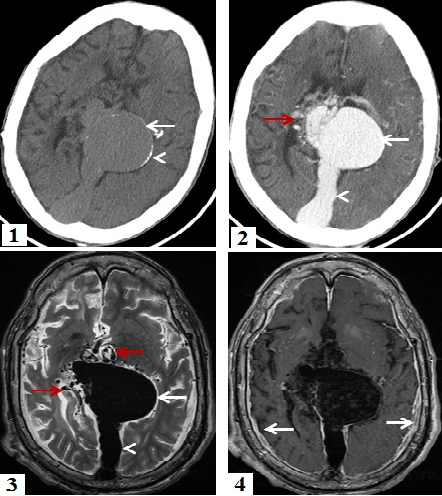

L'anévrysme de la veine de Galien est une affection congénitale rare, représentant moins de 1 % des malformations artério-veineuses intracrâniennes. Il résulte de l'absence de différenciation en système artério-veineux mature, entre 7 et 12 SA, d'une veine embryonnaire primitive, médiane qui draine les plexus choroïdes primitifs. La majorité des cas de malformation anévrysmale de la veine de Galien sont diagnostiqués en périodes anténatale, néonatale ou post- natale, le diagnostic à l'âge adulte est exceptionnel. Le tableau cliniqueà tout âge peut inclure: insuffisance cardiaque, retard psychomoteur, hydrocéphalie et crises d'épilepsie. Le traitement de référence est l'embolisation réalisée à quelques mois de vie mais le pronostic reste redoutable. Nous rapportons le cas d'un homme, âgé de 38 ans, admis aux urgences dans un tableau d'état de mal épileptique avec un syndrome méningé à l'examen clinique. Une TDM cérébrale a objectivé unemasse de la région pinéale, présentant des calcifications périphériques, rehaussé intensément après injection du produit de contraste en rapport avec une volumineuse dilatation anévrysmale de la grande veine de Galien. L'IRM cérébrale a montré cet anévrysme qui mesure 50 x 50 x 40 mm, associé à une dilatation du sinus droit et de multiples dérivations veineuses péri-anévrysmales avec épaississement et rehaussement dure-mérien régulier et diffus en rapport avec une méningite bactérienne confirmée par le bilan biologique. Vu qu'il n'y avait pas de signes d'hypertension intracrânienne ni d'hydrocéphalie, le patient a reçu un traitement médical de sa méningite associé à un traitement antiépileptique avec une bonne évolution clinique.